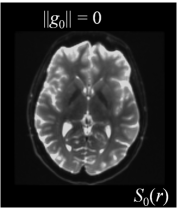

Six axial DW measurements and one non-DW image are shown in Figure 1, along with the corresponding magnetic field gradients . Note the difference in intensity values for different gradient directions.

| (a) | (b) | (c) | (d) |

| (e) | (f) | (g) | (h) |